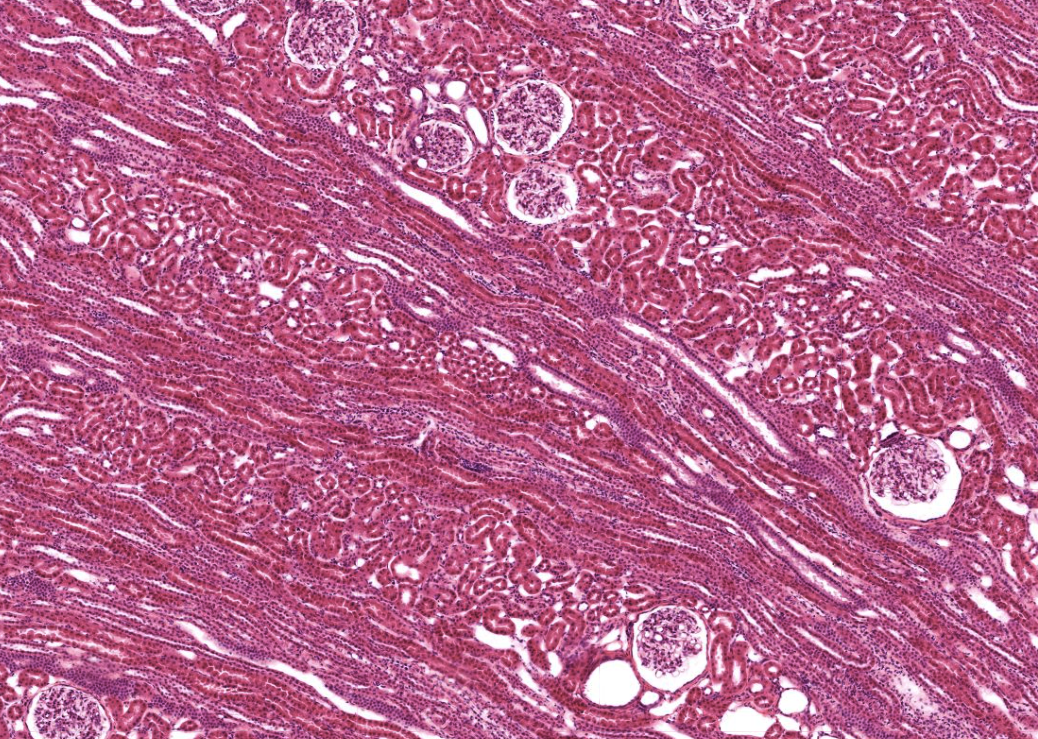

Märgstråle

• Ser ut som tuber som går mellan bark och märg.

• Namnet är lite missvisande då de ligger i barken, inte i märgen.

• I barken mellan kapsel och märgen.

• Leder primärurin genom tubuli från barkens Nefron mot märgen.